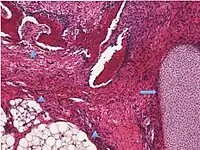

| Surface epithelial-stromal tumor | Serous tumor | 25% | 18.5% | Benign serous tumors of the right ovarian cyst are thinwalled unilocular cysts that are lined by ciliated pseudostratified cuboidal or columnar epithelium.[6] | ![]() |